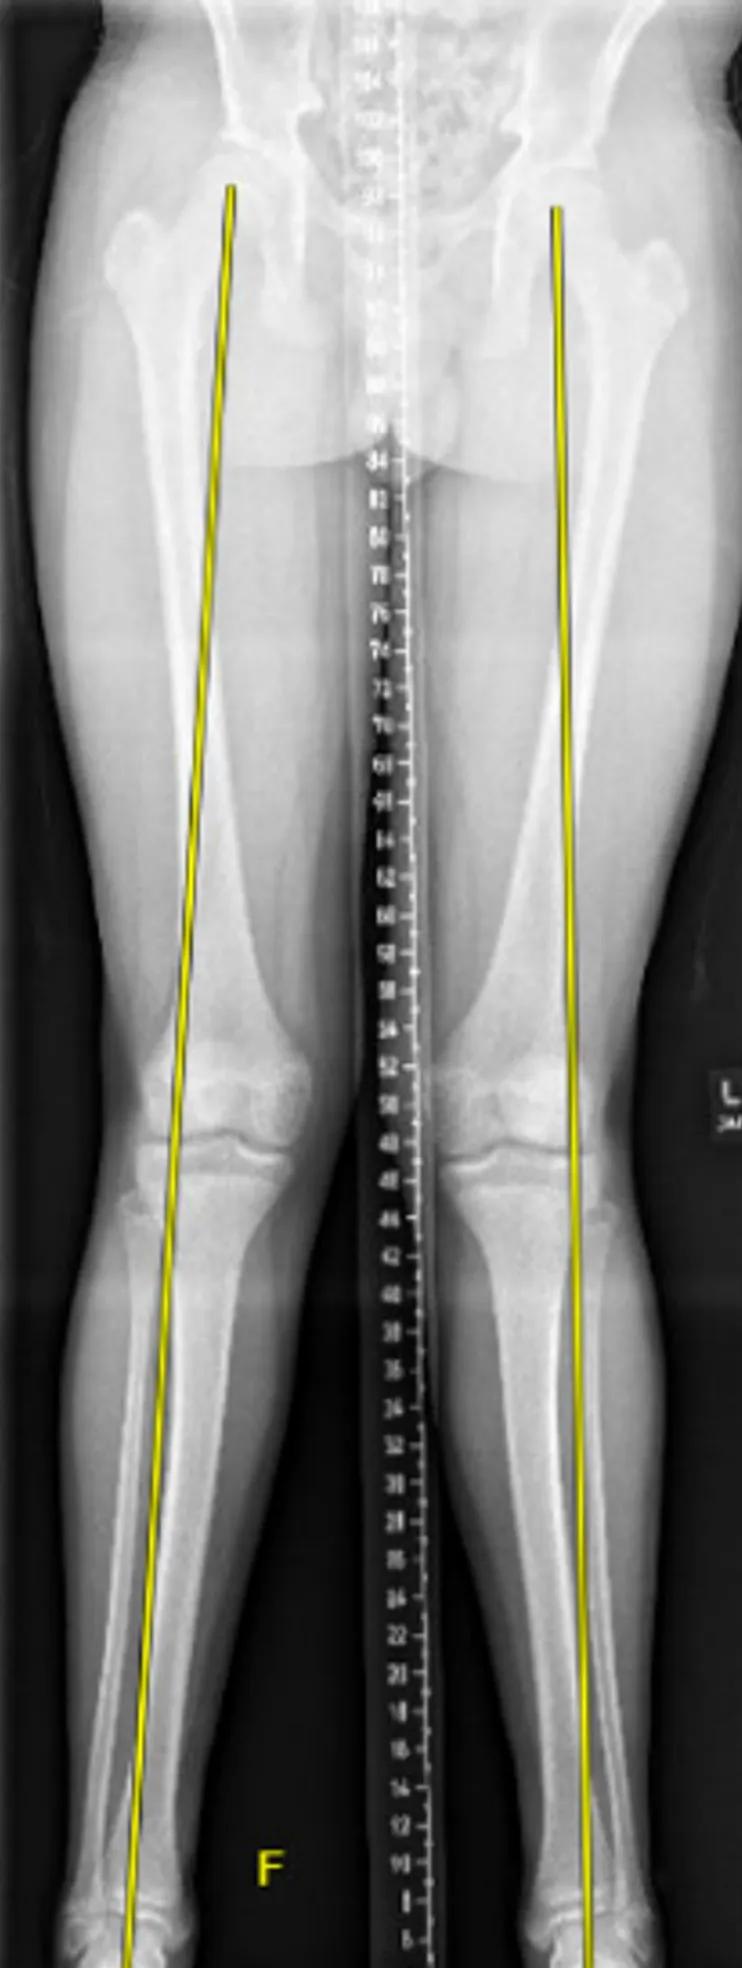

A 14-year-old male presented with complaints of progression of genu valgum, with his left knee more pronounced than his right. The mechanical axes passed through the lateral knee bilaterally.

Due to the predominantly femoral-induced genu valgum, as well as more significant deformity on the left side with questionable growth potential remaining, the decision was made to proceed with bilateral medial distal femur and left medial proximal tibia transient hemiepiphysiodesis with tension-band plating.

X-ray of patient with tension-band plating

The patient was followed postoperatively every four months with full-length bilateral lower extremity radiographs to assess for correction and timing of plate removal. After approximately one year of growth, the patient achieved a neutral mechanical axis, and plates were removed.

X-ray of patient with neutral mechanical axis